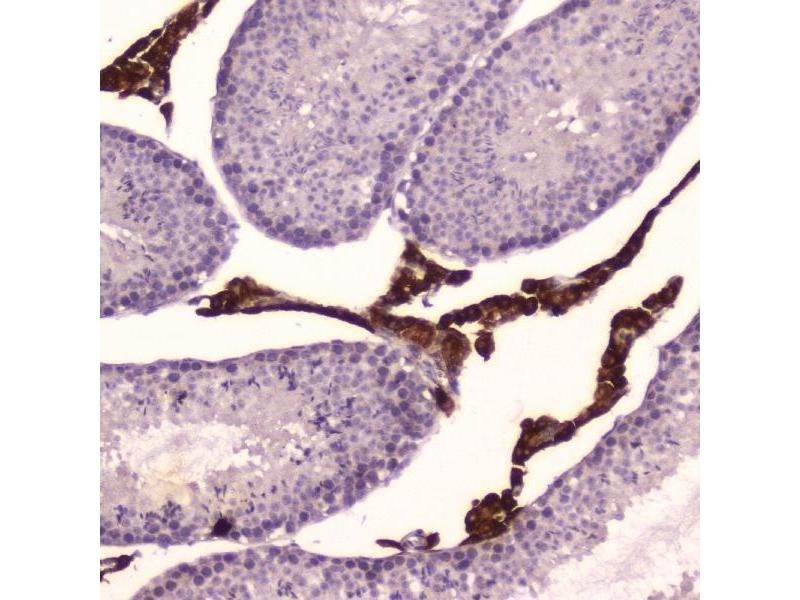

CYP17A1 Reactivité: Souris, Rat WB, ELISA, IHC (p) Hôte: Lapin Polyclonal unconjugated

Pubmed 3 références

N° du produit ABIN720071